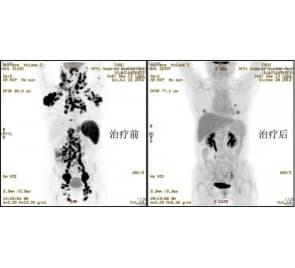

作为江苏省临床重点专科肿瘤学科带头人,郑骏年教授还带领肿瘤中心开展多项临床肿瘤生物治疗。目前徐医附院常规开展的肿瘤生物治疗、基因治疗项目有,自体免疫细胞治疗;肿瘤p53基因治疗;肿瘤抗血管生成治疗;肾癌、肺癌、乳腺癌、多发骨髓瘤、胃肠道肿瘤分子靶向治疗。其中自体免疫细胞治疗,是将肿瘤患者自身的免疫细胞分离,在体外用各种药物、技术刺激,让患者自己的免疫细胞数量增加、功能增强。对清除患者体内肿瘤残留病灶、防止复发、改善生活质量、延长生存时间具有重要作用。

早在1990年国外刚刚起步时,徐医附院即开始自体免疫细胞治疗肿瘤临床应用,治疗200余例患者,取得满意效果。2004年微创介入治疗联合自体免疫细胞治疗中晚期肝癌有效率达91.6%。2008年徐医附院斥巨资新建符合国际GMP标准的自体免疫细胞制备室。实验室现有专门人员12名,其中博导、教授2名、主任医师2名、博士4名、硕士6名。雄厚的技术力量,先进的设备,使实验室具备每月治疗患者100人次能力。

目前,徐医附院常规应用自体免疫细胞治疗各种肿瘤患者,包括黑色素瘤、乳腺癌、胃癌、结直肠癌、肝癌、胰腺癌、肾癌、前列腺癌、膀胱癌、宫颈癌、卵巢癌、肺癌、头颈部肿瘤、白血病,在防止肿瘤术后转移复发,延长缓解期方面,取得确切疗效。